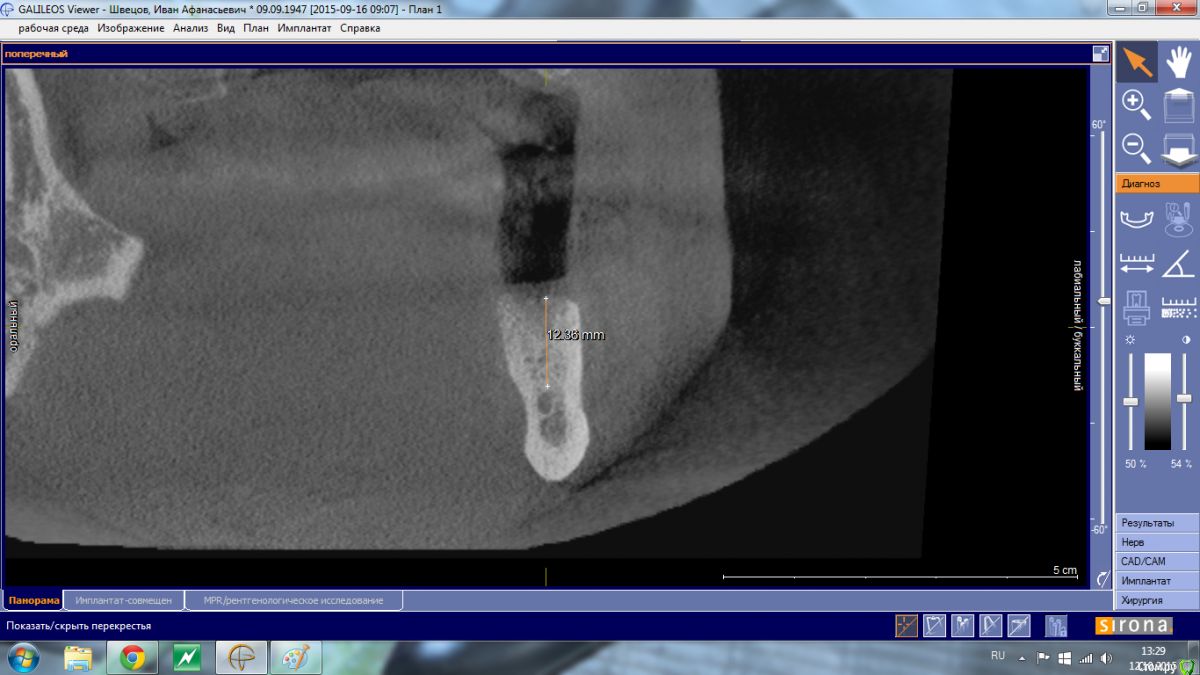

Shakirbura Опубликовано 12 октября, 2015 Автор Поделиться Опубликовано 12 октября, 2015 Снимок до имплантации.Сверло уперлось в 8-9 мм, что для меня было неожиданностью Ссылка на комментарий

АнтонТЛТ Опубликовано 13 октября, 2015 Поделиться Опубликовано 13 октября, 2015 Снимок до имплантации.Сверло уперлось в 8-9 мм, что для меня было неожиданностьюСкорее всего уперлись в подъязычное поднутрение, резцы с парестезией? 2 Ссылка на комментарий

Shakirbura Опубликовано 13 октября, 2015 Автор Поделиться Опубликовано 13 октября, 2015 Скорее всего уперлись в подъязычное поднутрение, резцы с парестезией?Семент от места имплантации до центра с парестезией. Имплантацию проводил под инфильтрационной анестезией, в момент проваливания пациент не сильно отреагировал. Говорит, что "как будто губу чем то задели". Ссылка на комментарий

АнтонТЛТ Опубликовано 13 октября, 2015 Поделиться Опубликовано 13 октября, 2015 Давайте контрольный снимок, если имплантат далеко от канала, то скорее всего травма + гематома (само пройдет), если имплантат в канале, то вынимать. 3 Ссылка на комментарий